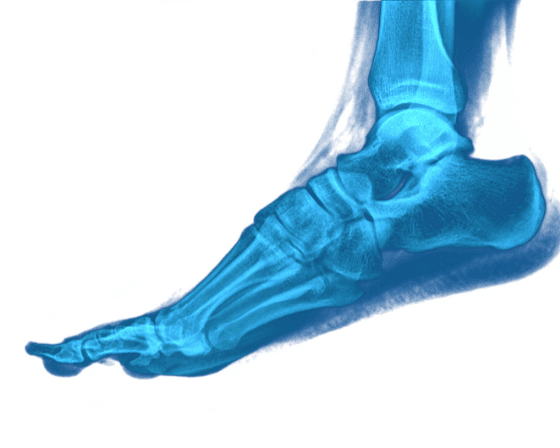

Toes aren't that attractive all the time. But if you wonder how important they are, of course, the answer will be in the affirmative, especially when it's about your big toe. Yes, that big toe is undoubtedly the most wanted amongst all, and you can realize it pretty well whenever you feel discomfort in your big toe. But unfortunately, it is that big toe that is quite active in getting itself into painful trouble for multiple reasons. Although we humans are born with the ability to tolerate a range of bodily pains during our lifetime, hurting that little big toe can be a real problem when it doesn't let you walk or stand with ease. So, if you find your big toe painful, it is essential to point out the problem and deal with it at the earliest so that your pain doesn't get into your nerves for sure. So, here are some of the reasons why your big toe might be hurting. Check them out and make the healing faster.